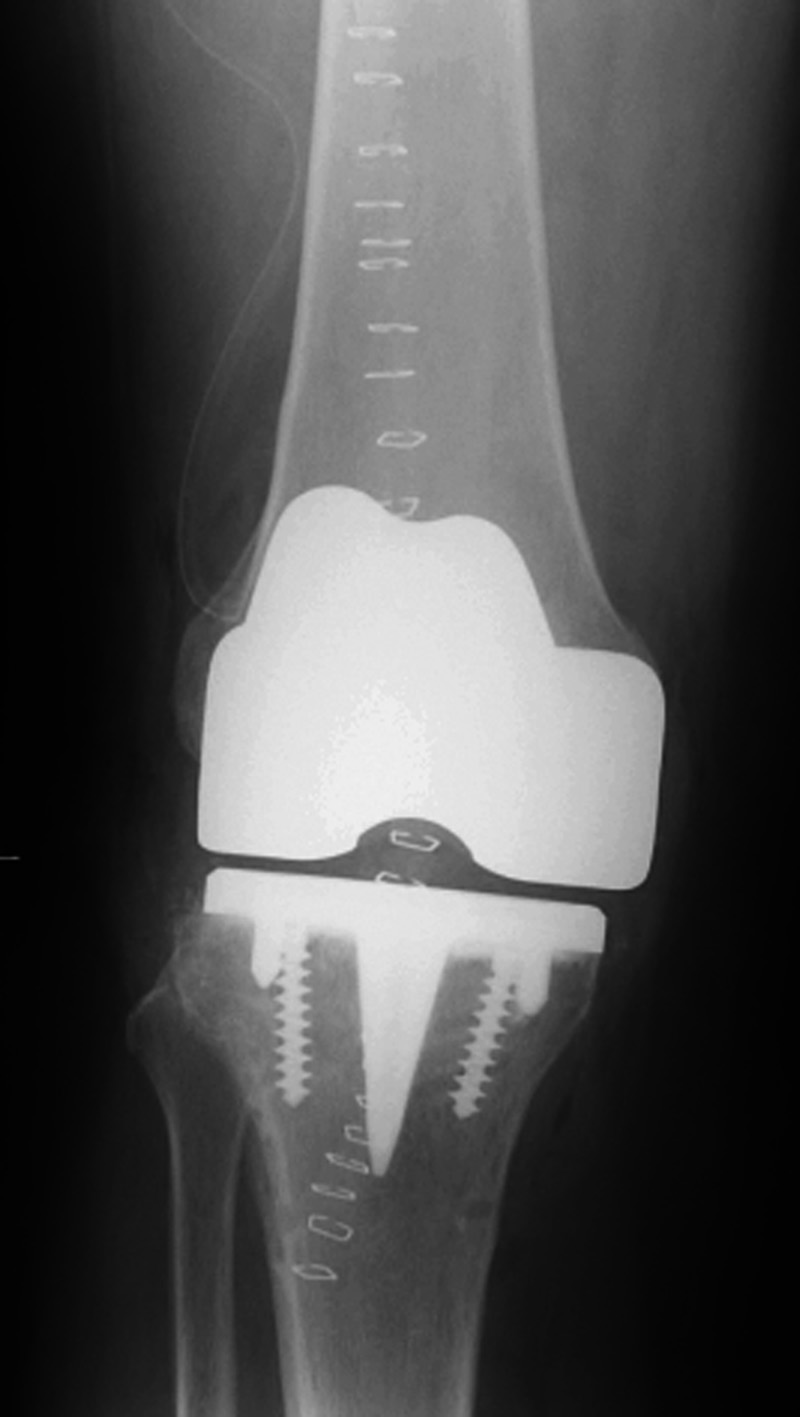

A somewhat less common total knee arthroplasty design is the varus-valgus constrained knee. These implants have a tall tibial post and a deep femoral box with a long ascending femoral stem (figure: constrained knee implant system; figure: varus valgus knee prosthesis). The femoral and tibial components are not linked, and these implants are referred to as unlinked constrained implants. They are most often used for revision arthroplasty, but are sometimes chosen for initial TKA placement (Lee, 2013).

Biomet Vanguard 360 Revision Knee System |

This replaced a loose prior total knee arthroplasty. The patellar button was left in place. A surgical drain is in place, and there is subcutaneous gas from the recent surgery. |